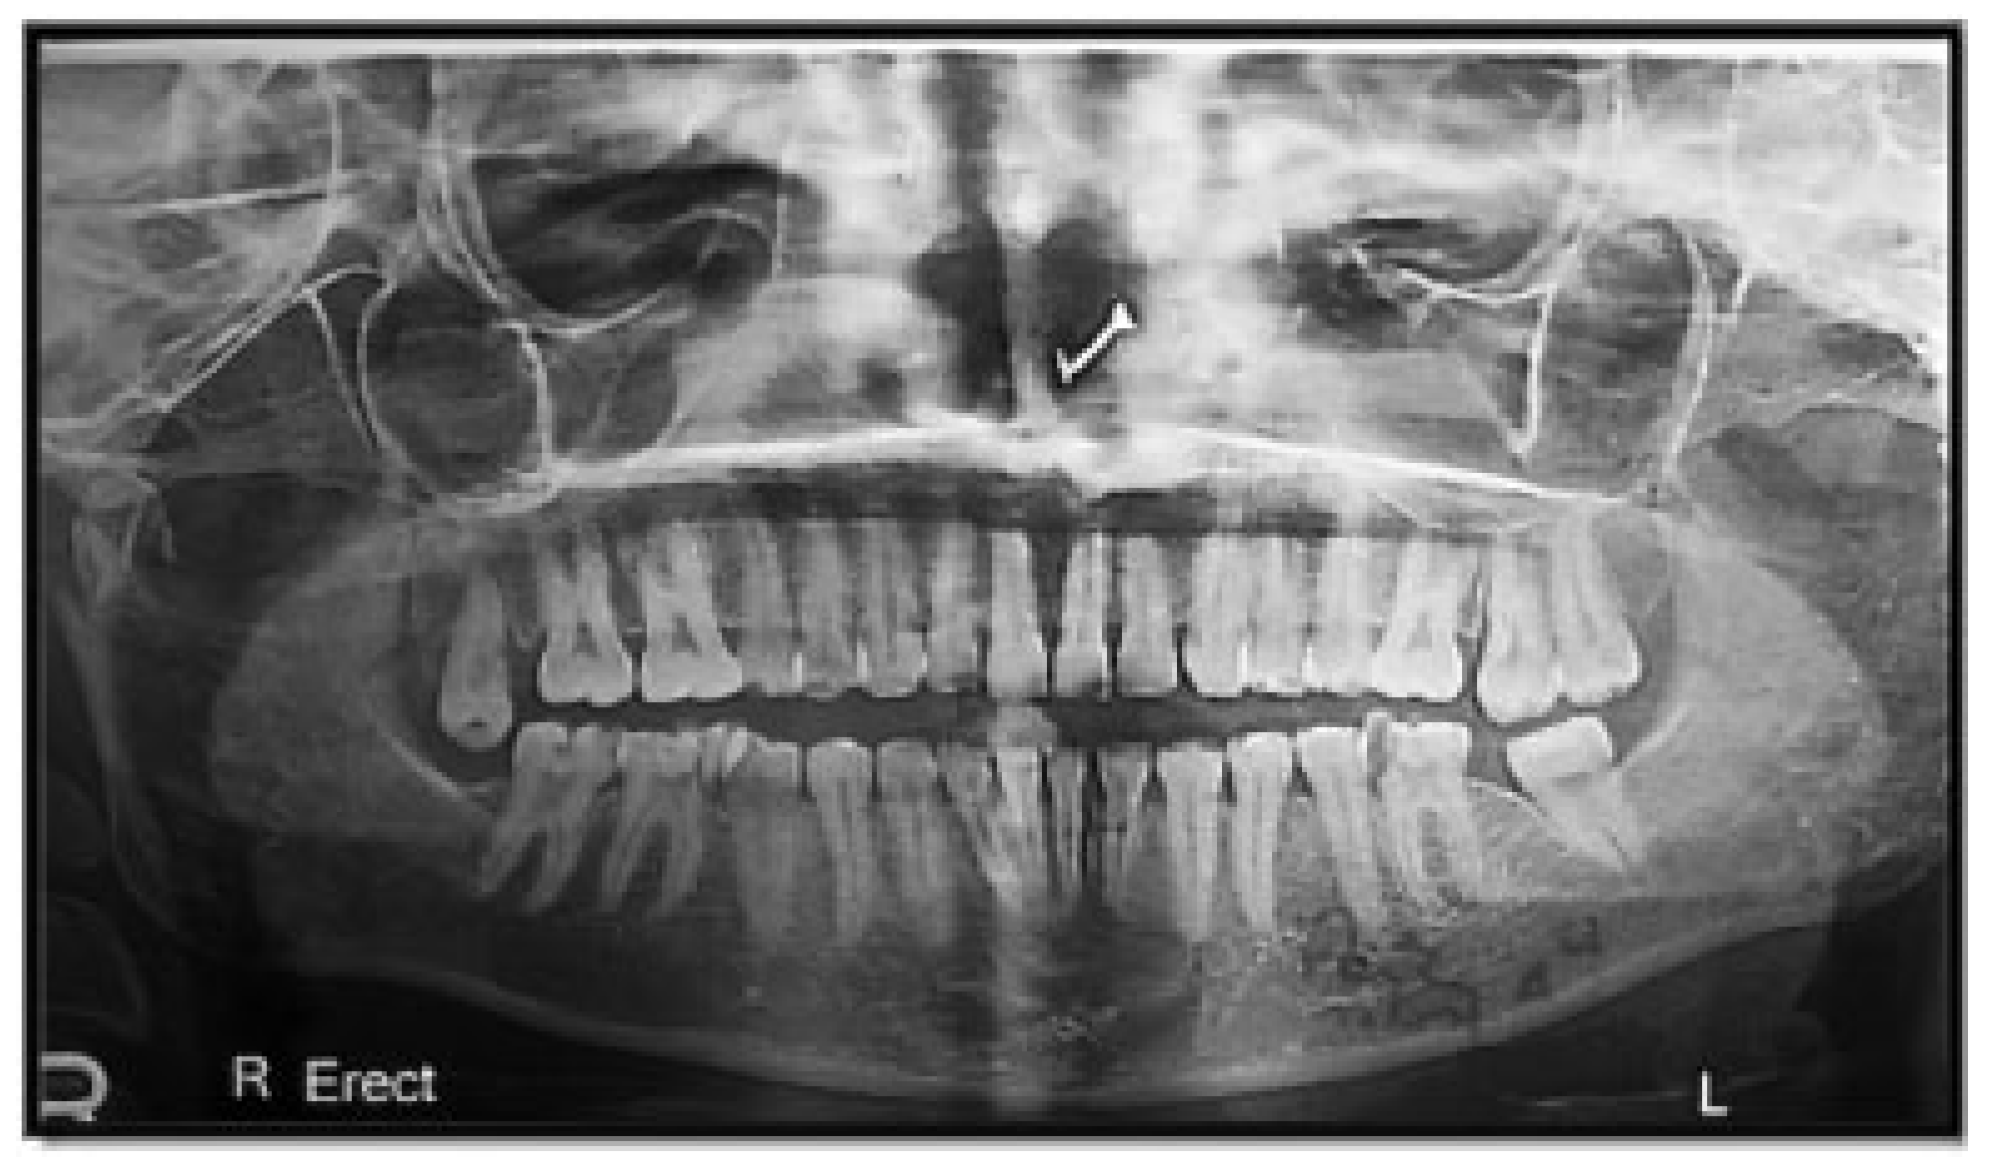

Figure 5. Angle fracture with the presence of impacted mandibular third molar.

Of the mandibular angle fractures, 146 patients (97.33%) had mandibular third molars and 4 patients (2.67%) did not have third molars. The presence of a mandibular third molar in angle fractures was statistically and significantly higher than in patients who did not have them.

Of the condyle fractures, 76 patients (58.46%) had absence of mandibular third molars, whereas 54 patients (41.54%) had third molars. The absence of a mandibular third molar in condylar fractures was statistically and significantly higher than in patients where third molars were present (Figure 5, Figure 6, Figure 7 and Figure 8; Table 4).